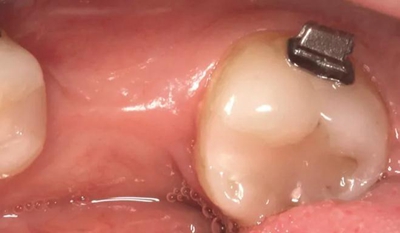

圖5a. 病例2中右下第一磨牙加速種植位點改建。初期排齊期間

圖5b. 術(shù)前臨床檢查

圖5c. 翻全厚瓣后,看到嚴重的牙槽嵴吸收

圖5g. 3 個月后完成了位點加速改建,近遠中向的修復空間和頰舌向的骨增量均增加

圖5h. 通過帶有一個后傾彎的鋼絲以及開放彈簧的半托槽距離輕加力實現(xiàn)了生物力學直立磨牙